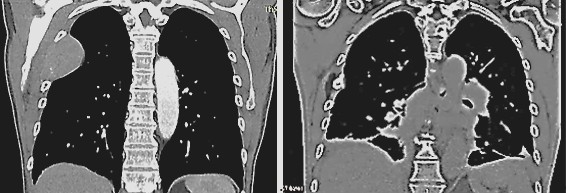

Fig. 4

Fig. 4: Metastasis at the 5th rib before TMI treatment (left) and disappearance of the metastasis six months after TMI treatment (right).

After five years of being free of symptoms, a rapidly growing, parotid-adjacent tumor on the right side occurred leading to facial palsy. An attempt to surgically remove the tumor was aborted due to risk to the facial nerve. An F-18-FDG PET whole-body CT scan revealed several disseminated hepatic metastases, osseous metastases in the pelvis and in the 5th dorsolateral rib. Histology of a biopsy from a hepatic metastasis as well as from a biopsy of the osteolytic region at the 5th rib, confirmed a recurrence of malignant melanoma. At this moment, the patient was in significantly reduced general condition with bad prognosis. The patient has been receiving oncological combination therapy with two immune checkpoint inhibitors, Ipilumab and Nivolumab. In parallel, an ultrasound-guided, once-weekly piezoelectric TMI treatment in the right parotid region was initiated. For this purpose, the PiezoWave2 device was used with a gel pad (shallow penetration depth Gelpad Nos. 5 and 10). The frequency used was between 2 and 4 Hz per treatment, with 3 Hz being the most common frequency. Depending on pain sensitivity and tolerance, 1000-1500 impulses were applied per session with an energy flux density of 0.12 mJ/mm². Following four immune checkpoint combination therapy sessions and eleven treatments with piezoelectric TMI treatment, a distinct regression after two months and a complete remission of the parotid-adjacent tumor as well as complete concomitant remission of the facial palsy occurred within four months (Fig. 3). Alongside the TMI treatment of the parotid region, TMI treatment of the pelvis metastasis using the PiezoWave2 device was performed simultaneously, precisely localizing the metastatic area measured in the PET-CT scan and based on patient-specific FEM simulation analyses. The deepest penetration depth was achieved with Gelpad 60, at a frequency of 2 Hz. Each treatment delivered 3000 impulses with an energy flux density of 0.35 mJ/mm². In a CT scan six months later, a significant reduction in bone metastases was observed as well as a complete remission of the hepatic metastases not directly treated with shock waves; however, a new pelvic metastasis had occurred. The metastasis at the 5th rib had disappeared (Fig. 4). Though the patient was affected by both the oncological disease and the side effects of the drug therapy, to consolidate and continue the evident therapeutic efficacy, regular TMI treatment of the new metastasis in the pelvic region was resumed with the OrthoGold100® device. The patient was treated 14 times over a six-month period. Each treatment involved a combination of the focused technique with the dark blue applicator and the non-focused technique with the yellow applicator. The deepest penetration depth was selected, along with energy flux density of 0.18 mJ/mm² or 0.27 mJ/mm², applying 2000 impulses per applicator, thus a total of 4000 impulses per session. After TMI treatment, native CT scans showed a distinct regression of the new pelvic metastasis and unchanged sclerosis of the known bone metastases.